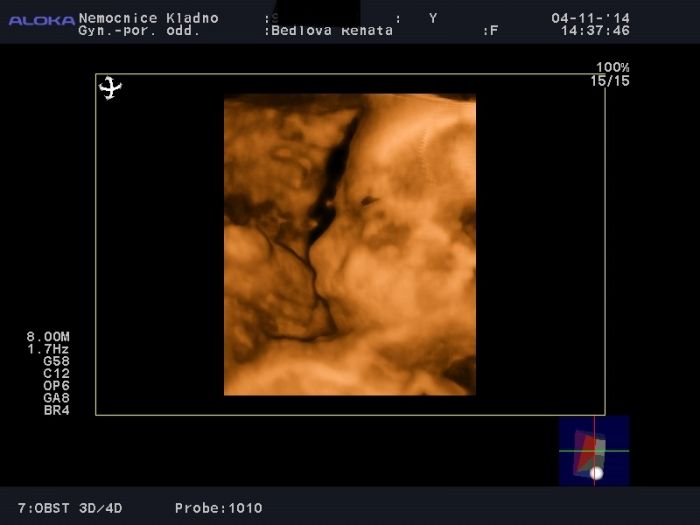

A 3D-4D ultrazvuk se moc nepovedl jelikož jsem prý málo průhladná no :-D. Prej se to občas stane, že to některý maminky, tak mají. Původně jsem měla platit 900,-, ale tím že nebylo toho moc vidět tak jsem měla slevu a stálo mě to jenom 400,-.

Stello ten UZ se dělá 3D, ale když si řekneš tak i 4D mě dělali oba. Ten 4D tam vlastně navíc slyšíš srdíčko jak bije. Fotku přidávám. Mám i krátký videa.